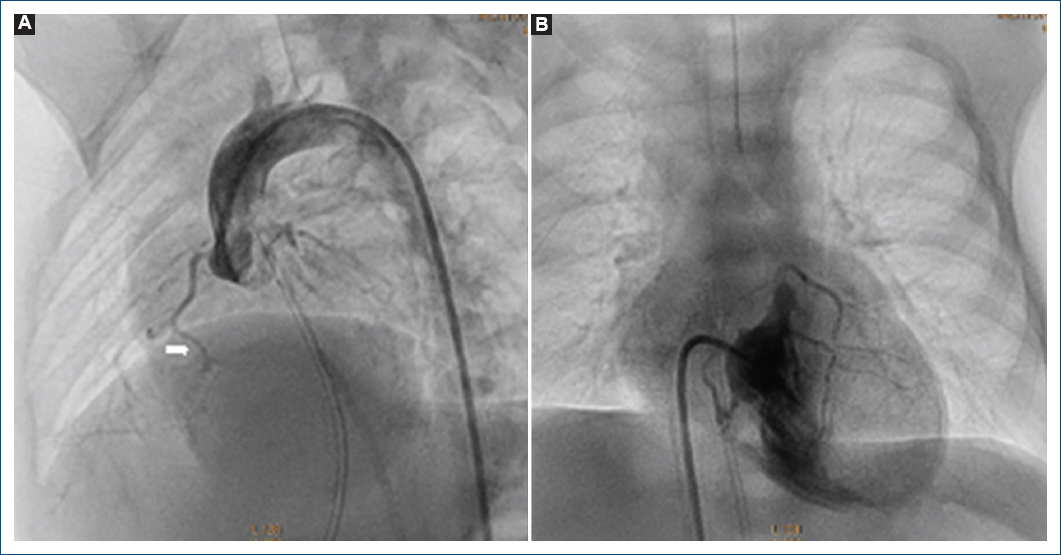

Figura 1 Ventriculografía derecha. Se observa atresia pulmonar con septum ventricular íntegro con conexiones ventrículo-coronarias, estenosis grave en el tercio proximal de la descendente anterior (flecha). A: proyección postero-anterior. B: proyección lateral izquierda.

Figura 2 Coronariografía izquierda. Se observa dilatación del tronco coronario izquierdo y estenosis crítica en el tercio proximal de la descendente anterior y las conexiones ventrículo-coronarias (flecha). A: proyección cuatro cámaras. B: proyección oblicua anterior derecha.